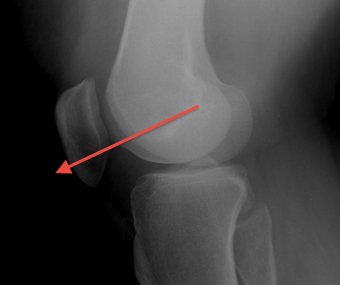

Dejour Crossover Sign

- lateral x-ray at 30o with condyles superimposed

- identify base of trochlea

Abnormal / Crossover

- line of floor of trochlea crosses lateral lip of condyle

- indicates trochlea is deficient proximally